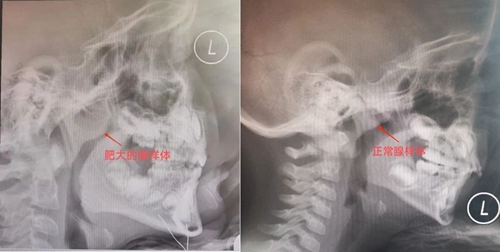

腺樣體又稱咽扁桃體,是位于鼻咽部的一團(tuán)淋巴組織。腺樣體可因炎癥的反復(fù)刺激出現(xiàn)病理性增生肥大,稱之為腺樣體肥大。正常生理情況下,兒童2~6歲時(shí)增生最顯著,10~12歲逐漸萎縮,成人基本消失。因此,腺樣體肥大主要集中在學(xué)齡前兒童。

腺樣體面容多因腺樣體肥大引起,肥大的腺樣體可使氣道變窄,從而影響通氣?;純狠p則打鼾張口,重則聽力下降,甚至引起面容改變(如門牙前突、露齒、齙牙、唇厚且外翻,臉型變長等),以及多動(dòng)、學(xué)習(xí)障礙等。